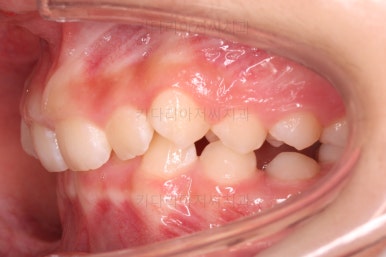

초진 시 입안의 모습입니다.

앞니가 안으로 굽어 들어간 양상인데요. 흔히 "옥니"라고 표현합니다.(뻐드렁니의 반대개념)

전반적으로 치열이 삐뚤삐뚤하고요.

오른쪽 상단 사진을 보시면 어금니의 높이와 앞니의 높이의 차이가 많이 나요.

앞니가 솟구쳐 있는 양상인데요.

그 이유 때문에 어금니로 다물었을 때 위아래 앞니가 많이 겹쳐서 아래 앞니가 아예 보이지 않는 상황이었어요.

이를 "과개교합"이라고 표현합니다.

그리고 전반적으로 아래 치열이 윗니에 비해 뒤로 밀려 있어서, 어금니의 맞물림이 좋지 못하고 듬성듬성해 보이는 상황이었어요.